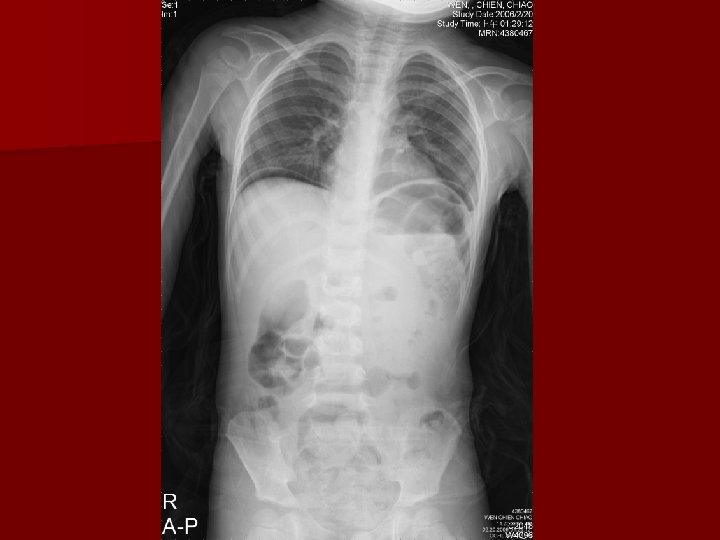

Pediatric Case Discussion R 2 Er Visit